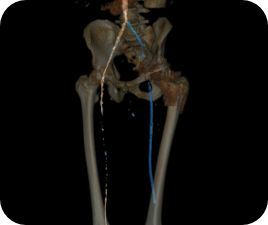

Die automatische Segmentierung von Knochen und Gefäßen und die Mittellinienverfolgung durch den Gefäßverschluss ermöglichen eine schnelle Planung anhand von präoperativen CT- oder MR-Bildern. Durch diese Kombination präoperativer CT- oder MR-Bilder mit Mittellinienverfolgung und Durchleuchtung in Echtzeit können Spezialisten außerordentlich gut sehen, wo die Rekanalisation vorgenommen werden muss und wo sich die Einstichstelle befindet, ohne die Kontrastmittelmenge erhöhen zu müssen.

Vessel ASSIST bietet eine präzise und einfache anatomische Segmentierung und genaue Gefäßquantifizierung anhand von 3D-Volumen. Zudem ermöglichen die erweiterte 3D-Roadmap und erweiterte Bildführungsfunktionen für die frontale und laterale Ebene das sichere Führen von Kathetern.